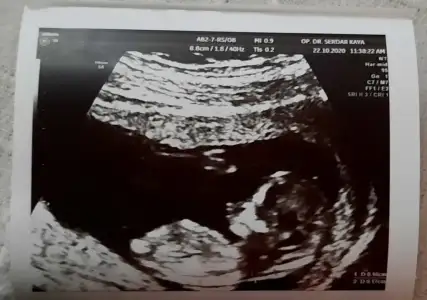

Merhaba Ikra meyra Ikra meyra canım, bir tahmin alabilir miyim ben de 13+2 olduk. :KK36:

Eklentiler

• 20201021_114201.webp

20201021_114201.webp

23,3 KB · Görüntüleme: 63

• 20201021_114209.webp

20201021_114209.webp

23,7 KB · Görüntüleme: 51

• 20201021_114216.webp

20201021_114216.webp

18,4 KB · Görüntüleme: 80